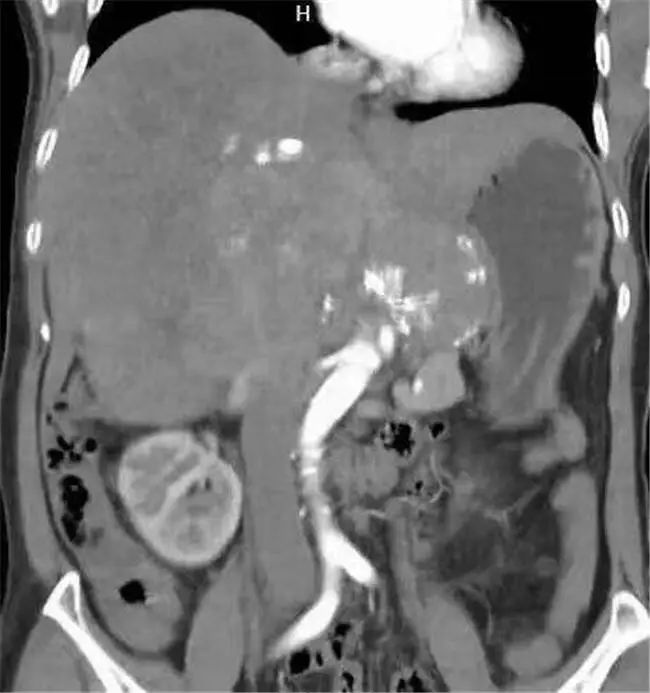

家人送医后CT检查显示:中、上腹巨大不均质肿物,填塞肝门,贴压胆囊、胰腺、右肾、门静脉、下腔静脉,考虑恶性。病人和家属立刻感到紧张和无助,虽在各大医院辗转求诊,均表示治疗意义不大。但病人和家属均不想放弃,怀着最后一丝希望,来到云南省第三人民医院肝胆胰外科就诊。

患者入院后,经过仔细检查后发现这名患者中上腹巨大不均质肿物已经填塞肝门,与肝实质分界不清,贴压胆囊、胰腺、右肾、门静脉、下腔静脉,手术操作的空间非常小。其次,患者身体基础条件十分不好,长期高血压,心肺功能极差,肝功能下降,手术难度极大。

6月5日8时,手术正式开始。江行带领专家手术组历时6个小时,实施了切除、重建、修补过程,最终,顺利完成巨大肿瘤切除+右半肝、全尾状叶切除术+胆囊切除术,成功从患者体内取出长约27厘米,重达4.21千克的肿瘤。